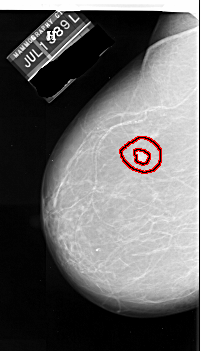

A_1090_1.LEFT_CC

LEFT_CC LINES 6316 PIXELS_PER_LINE 3601 BITS_PER_PIXEL 16 RESOLUTION 42 OVERLAY

FILE: A_1090_1.LEFT_CC.OVERLAY

TOTAL_ABNORMALITIES 1

ABNORMALITY 1

LESION_TYPE MASS SHAPE IRREGULAR MARGINS SPICULATED

ASSESSMENT 5

SUBTLETY 4

PATHOLOGY MALIGNANT

TOTAL_OUTLINES 2

BOUNDARY

CORE